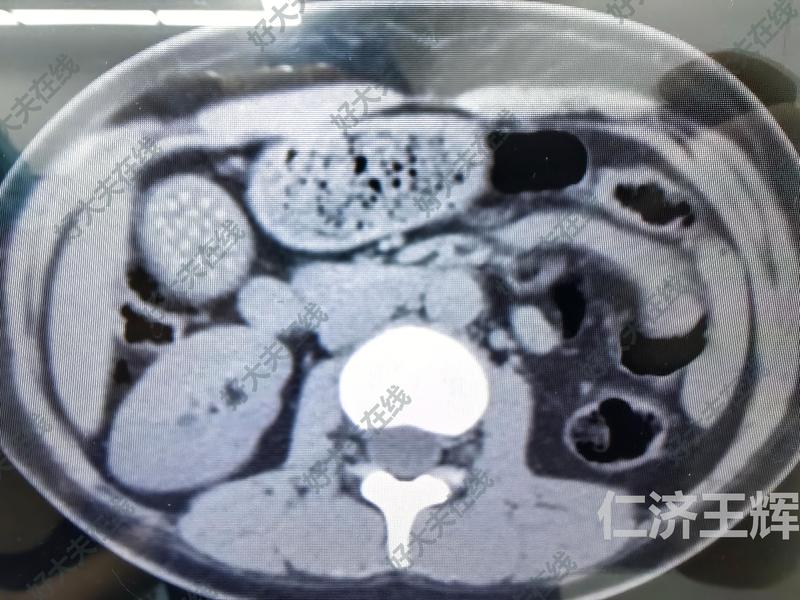

治療前患者30歲女性,右上腹脹痛半年余,b超發(fā)現(xiàn)膽囊壁增厚,膽囊多發(fā)小結(jié)石治療中經(jīng)臍孔處行單孔腹腔鏡膽囊切除手術(shù),共耗時(shí)30分鐘,術(shù)中無(wú)出血。治療后治療后1月患者恢復(fù)良好,無(wú)任何不適,大便如常,自覺(jué)傷口無(wú)任何感覺(jué),未見(jiàn)明顯疤痕。